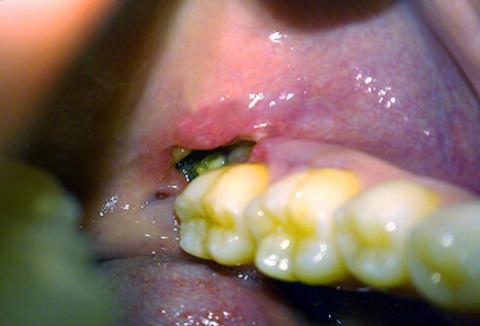

After a tooth is pulled, a protective blood clot forms in the empty socket. This clot is a biological bandage, shielding the underlying bone and nerve endings and providing a framework for new tissue to grow. A dry socket occurs when this crucial clot dislodges or dissolves too early, leaving the sensitive bone and nerves painfully exposed.

This is not just minor discomfort. Patients describe it as a severe, throbbing pain that can radiate from the jaw to the ear, temple, or neck on the same side of the face. Other tell-tale signs include an empty-looking socket, visible bone, and a persistent bad taste or foul breath. The pain typically begins a few days after the extraction and will not resolve on its own.